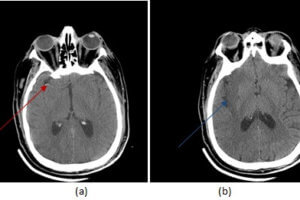

Dense MCA sign in R hemisphere

Early Signs of Stroke on CT

Despite its poor sensitivity for detecting embolic strokes, head CT scan remains the initial imaging modality in the work up of suspected acute stroke. The rationale is to initially rule out hemorrhagic... Read more »